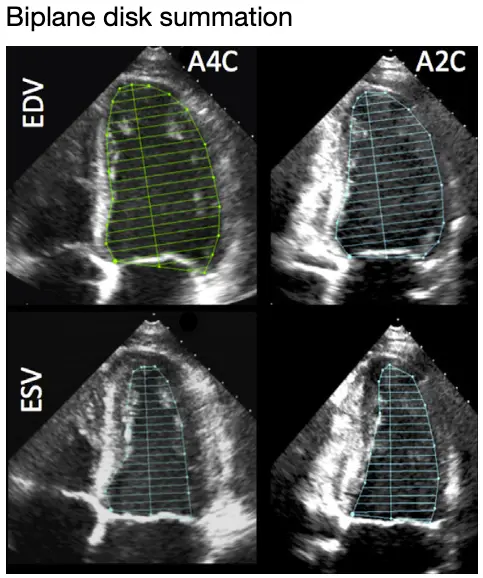

- 🌟 Biplane Method of Disks (MOD) summation (modified Simpson’s rule)

- recommended 2D echocardiographic method by the 2015 Chamber Quantification Guidelines committee

- “At the mitral valve level, the contour is closed by connecting the two opposite sections of the mitral ring with a straight line. LV length is defined as the distance between the middle of this line and the most distant point of the LV contour.” (2015 Guidelines)

- Tip: A4C and A2C lengths should be within 10% of each other, otherwise suggests foreshortening

- ⚠️ make sure you are avoiding papillary muscles, false chords, etc. when doing tracing